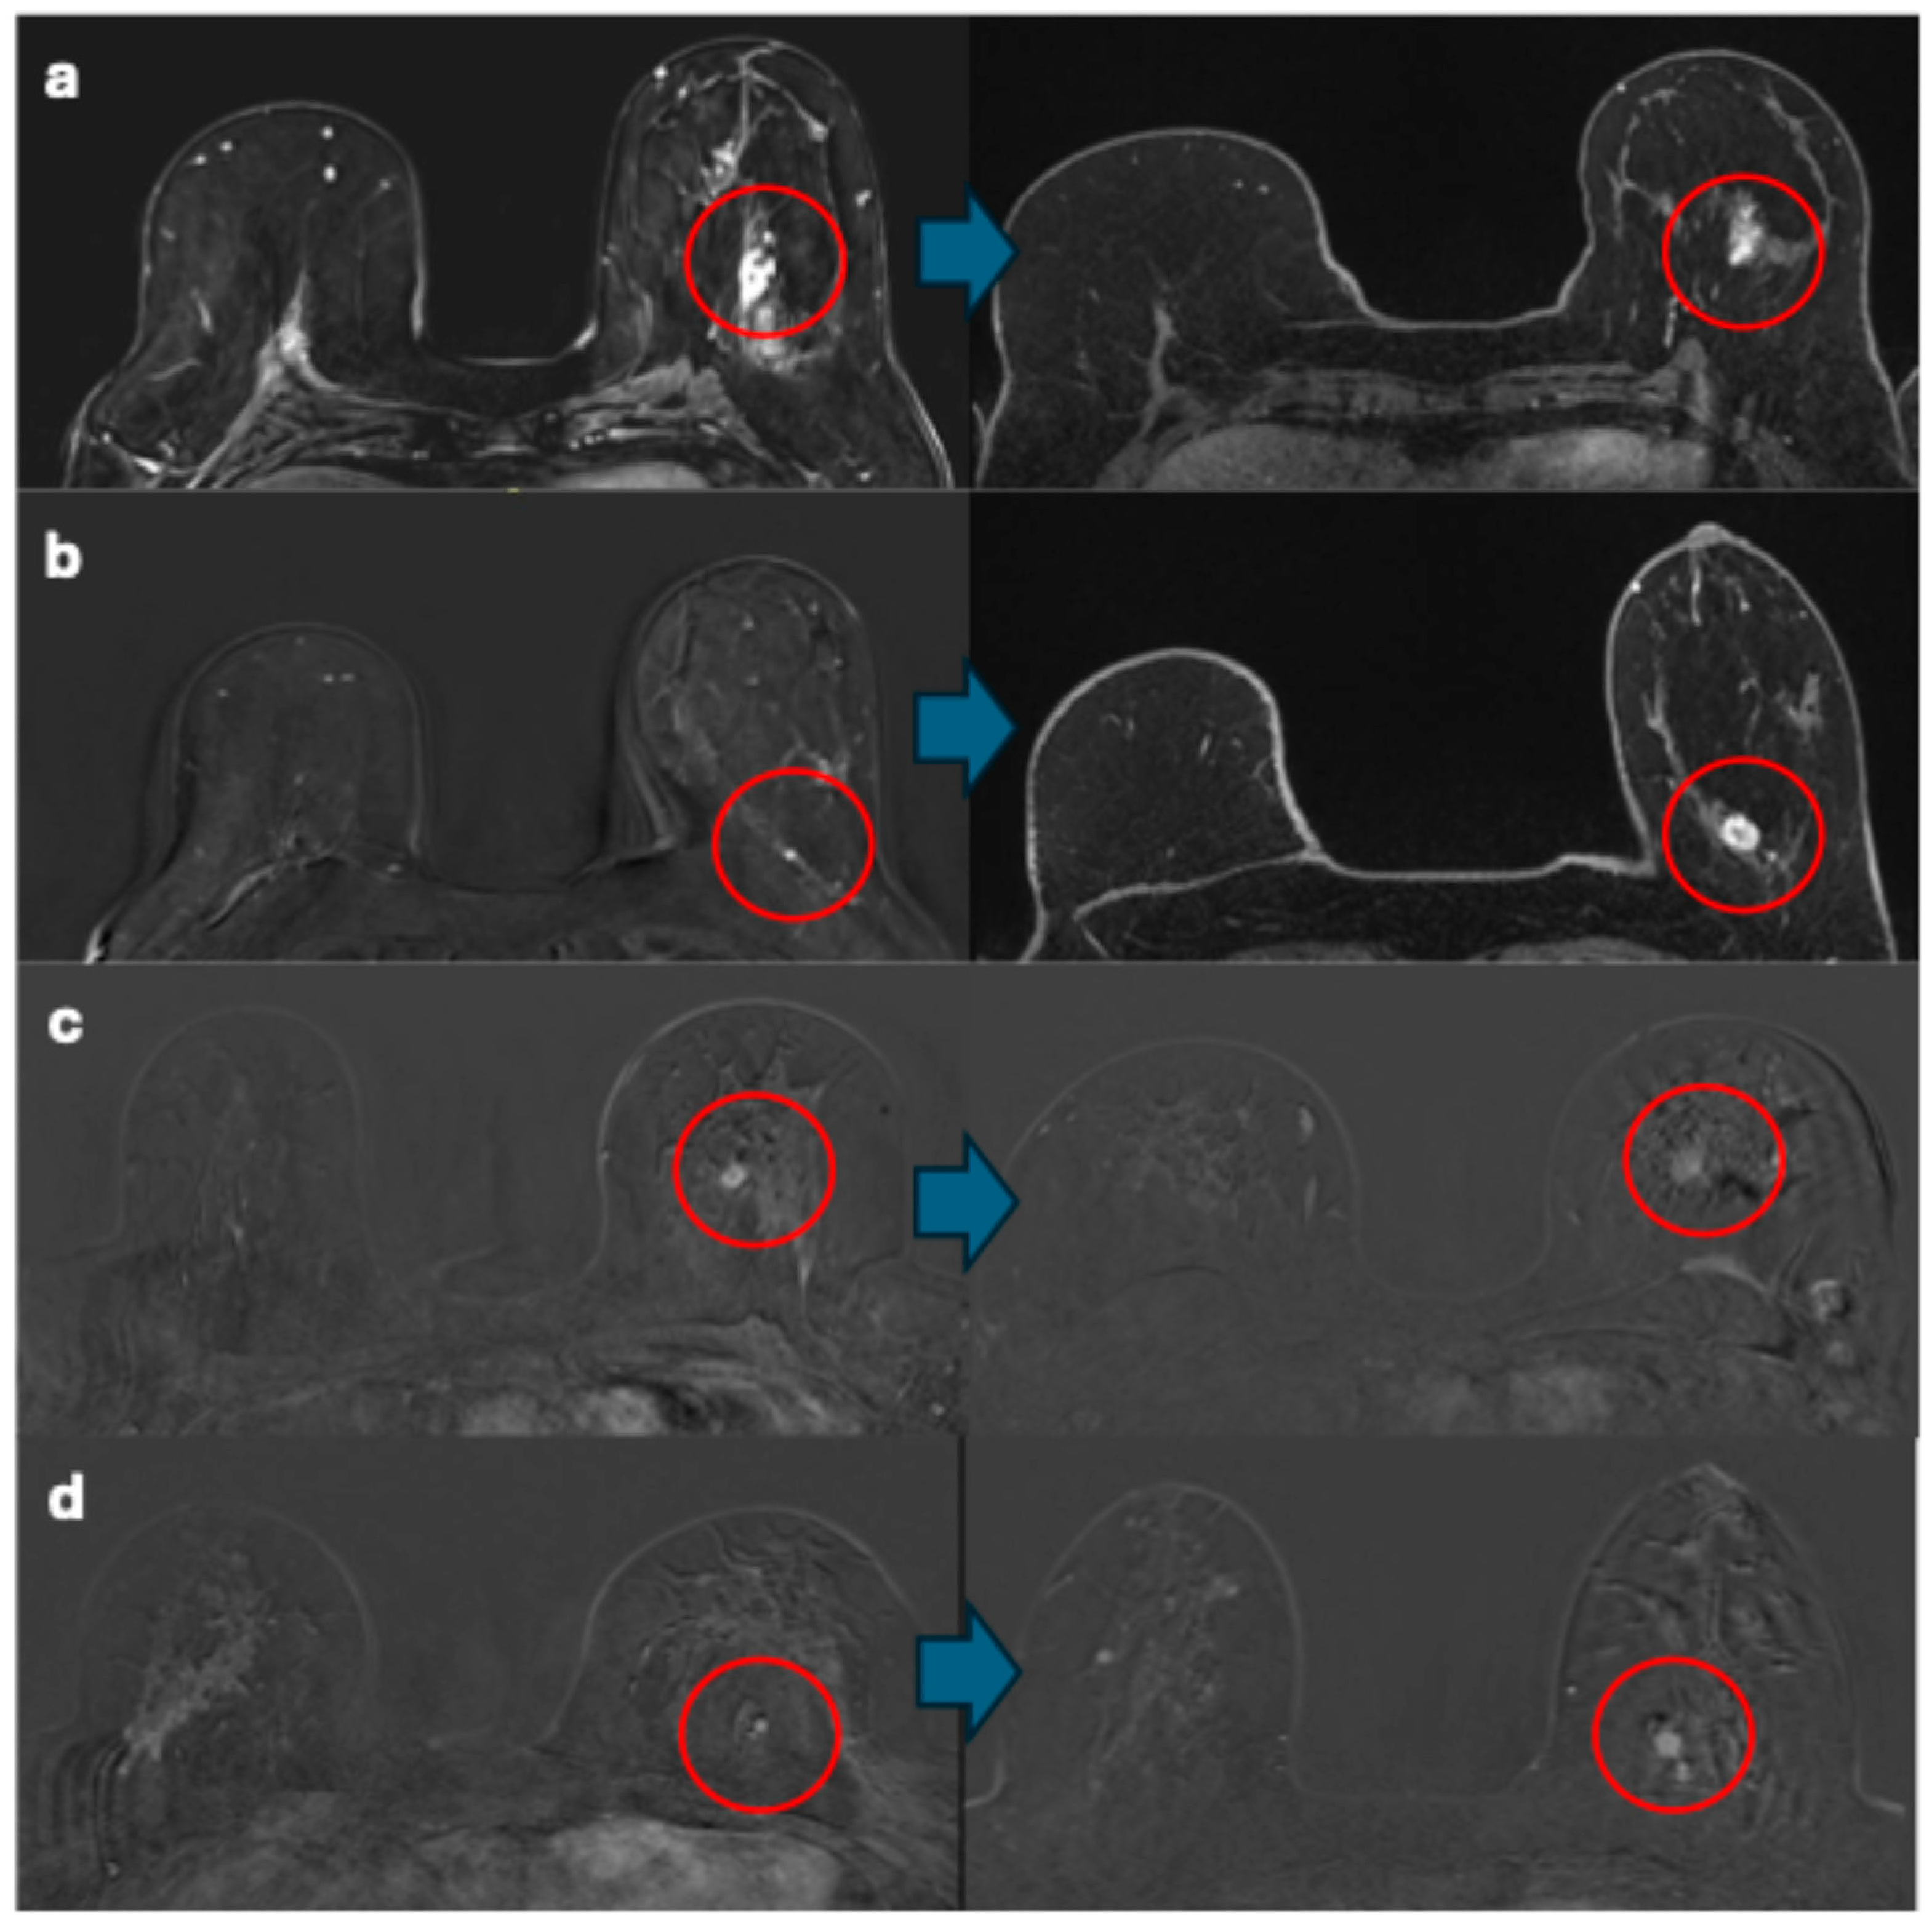

3.2. Magnetic Resonance Imaging Features and Corresponding Pathology Outcome of Breast Cancers

| Features | Breast Cancers (N = 9) Described at MRI Re-Evaluation | |

|---|---|---|

| Background parenchymal enhancement | ||

| Minimal or mild | 2/6 | |

| Moderate or marked | 4/6 | |

| Lesion type | ||

| Mass | 5 | |

| Shape | Round | 1/5 |

| Oval | 1/5 | |

| Irregular | 3/5 | |

| Margins | Circumscribed | 1/5 |

| Irregular | 4/5 | |

| Enhancement | Heterogeneous | 4/5 |

| Rim enhancement | 1/5 | |

| Non-mass enhancement | 4 | |

| Distribution modifiers | Focal area | 2/4 |

| Segmental | 1/4 | |

| Regional | 1/4 | |

| Internal enhancement | Heterogeneous | 2/4 |

| Clumped | 2/4 | |

| Kinetic curve assessment: initial phase 1 | Fast | 7/7 |

| Kinetic curve assessment: delayed phase 1 | Washout | 7/7 |

| Type of breast cancer | NST | 6/9 |

| ILC | 1/9 | |

| DCIS | 1/9 | |

| Other | 1/9 | |

| ER 2 | Positive | 3/6 |

| Negative | 3/6 | |

| PR 2 | Positive | 3/6 |

| HER2 2 | Positive | 1/6 |

| Negative | 5/6 | |

| Triple negative 2 | No | 3/6 |

| Yes | 3/6 | |

| Grade 2 | 1 | 0/6 |

| 2 | 3/6 | |

| 3 | 3/6 |